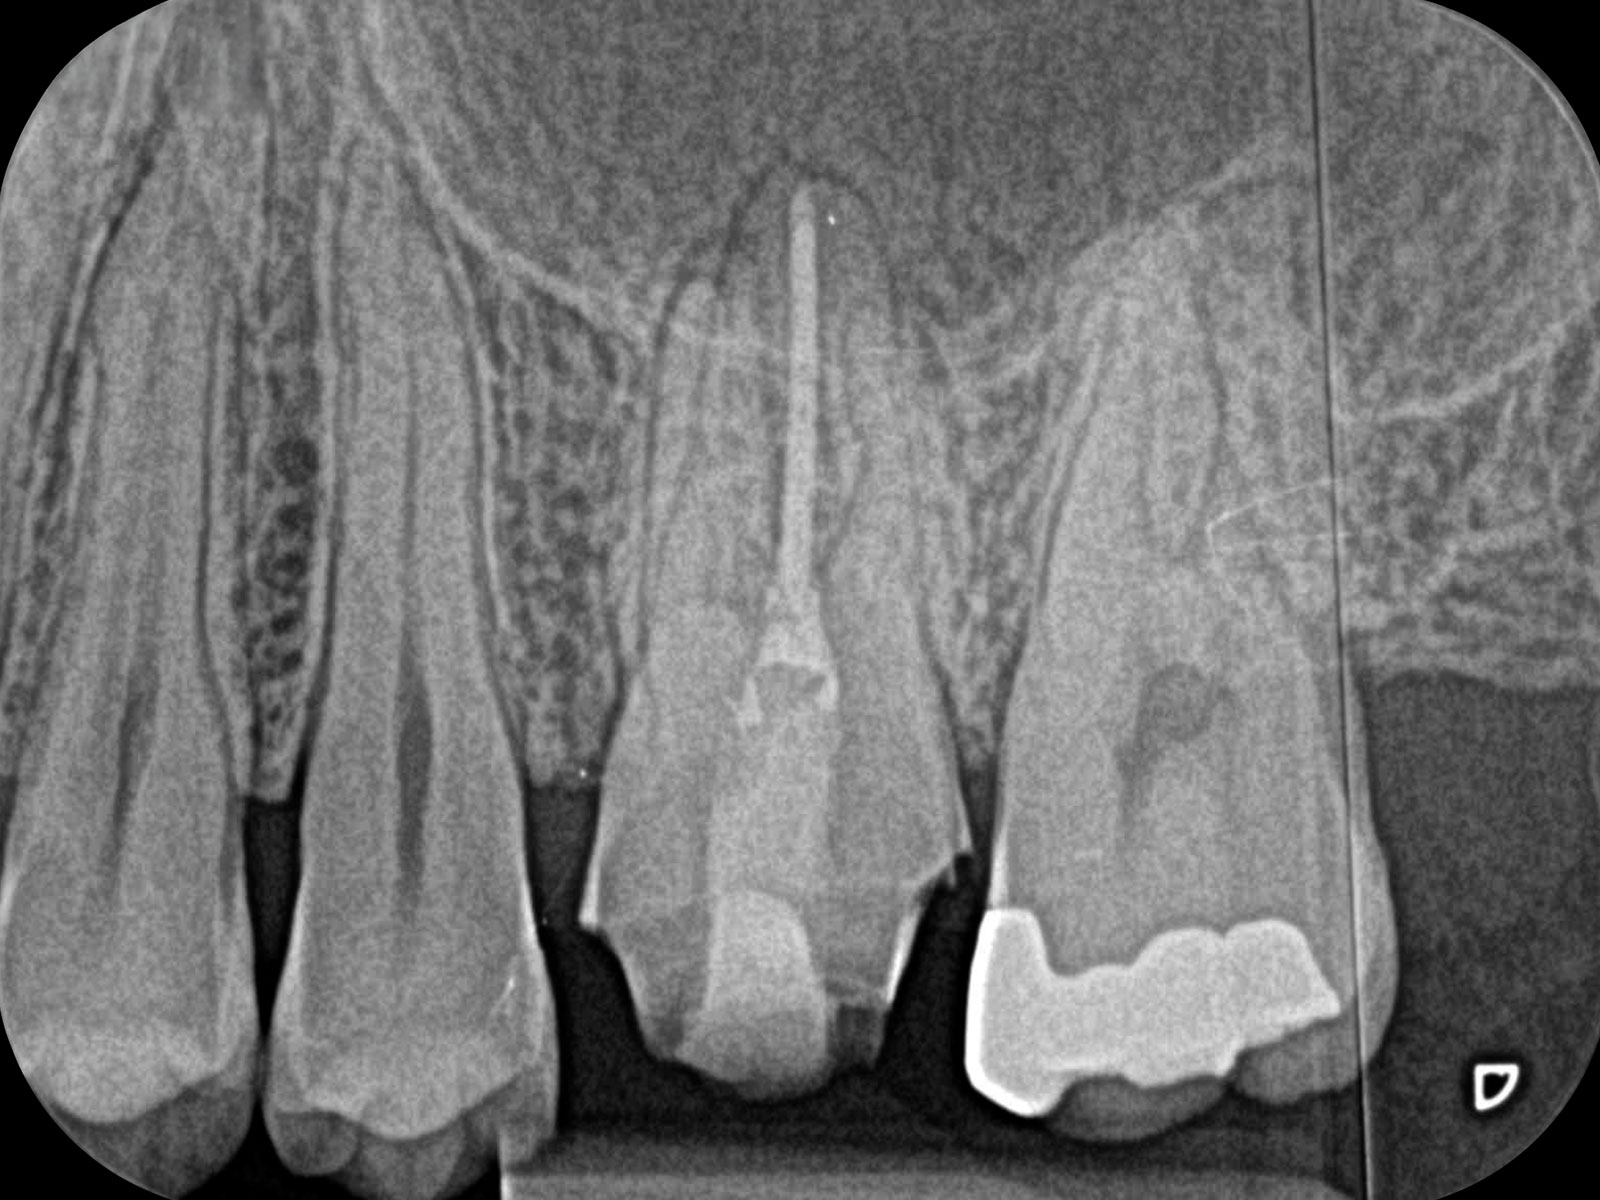

丸の部分が病巣です。CT画像によって、左の画像(Before)では黒く映っている病巣が右の画像(After)ではなくなっていることが確認できます。レントゲン画像ですと、ここまでクリアに写りませんので、病巣を見落としてしまう可能性があります。